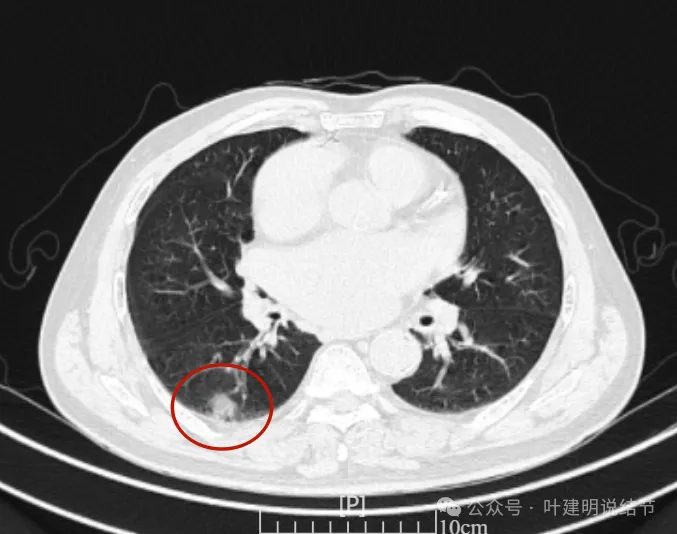

再看2024年6月时的影像:

左下也考虑良性,与2022年无明显变化。

右下新增病灶,混合密度,整体轮廓较清,瘤肺边界欠清。